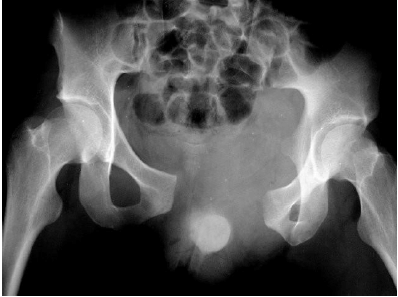

A imagem, abaixo, demonstra comprometimento: